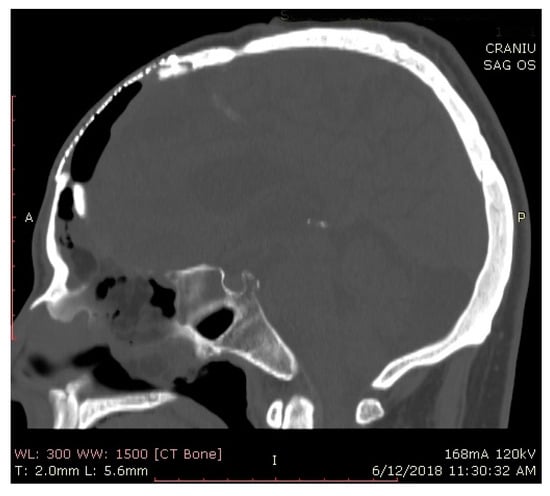

2.2. Surgical Approach and Reconstruction Technique